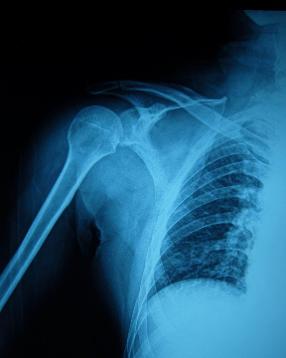

♥肱骨大结节骨折

肱骨大结节骨折,少数为单独发生,大多系肩关节前脱位时并发,故诊断时应注意有无肩关节脱位。